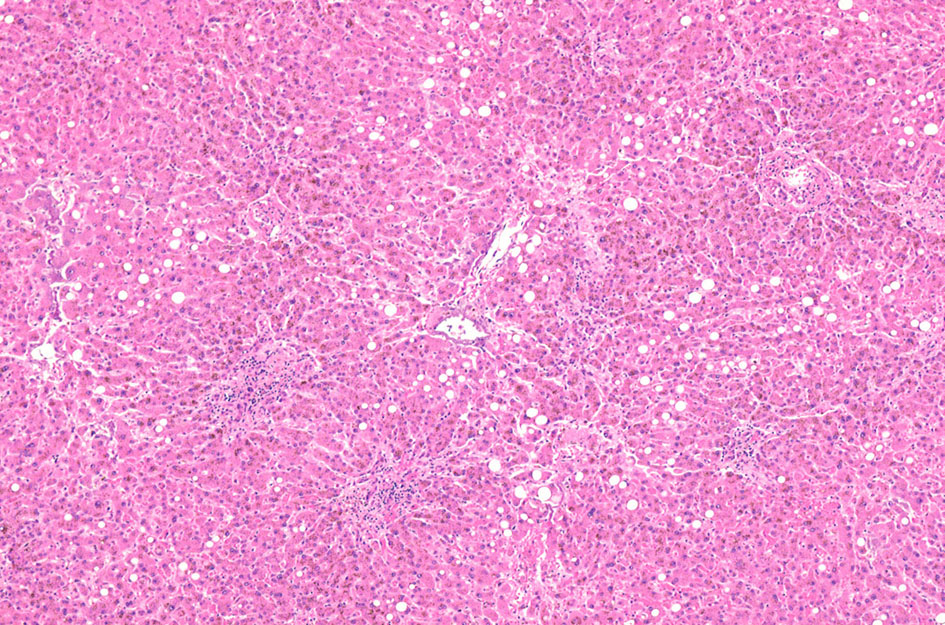

70歳代男性の骨髄。hypercellular marrow. M/E=1-2, erythropoietic hyperplasiaを認める(1, 2). megaloblastosisが出現。(3).

Mgkは成熟大型のものが多い(4). 単核, 小型球状核のMgkも認められる(5)

骨髄塗抹標本と組織(clot section)の鉄染色(クリックで大きな画像がみられます) ring sideroblastは鉄顆粒が核周囲にまとわりつくように見える赤芽球として認められる。Hb合成の乏しい幼若な大型赤芽球では認められる鉄顆粒は少ない。